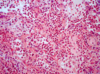

¿Cuál es el factor/causa de neumonía adquirida en la comunidad? En caso de que no sea ese y te diga que el px es drogadicto intravenosos

Neumococo o Streptococo pneumoniae S. Aureus Nota: foto- alveolos llenos de neutrófilos- neumonía

Px con absceso pulmonar y empiema (derrame pleural purulento) me hace pensar en: Nota: Absceso pulmonar- El absceso pulmonar es una infección necrosante del pulmón caracterizada por una lesión cavitaria repleta de pus.

S. Aureus. Nota: S,Aureus no es frecuente pero si px dragadito es una opción. Nota: foto- alveolos llenos de neutrófilos- neumonía